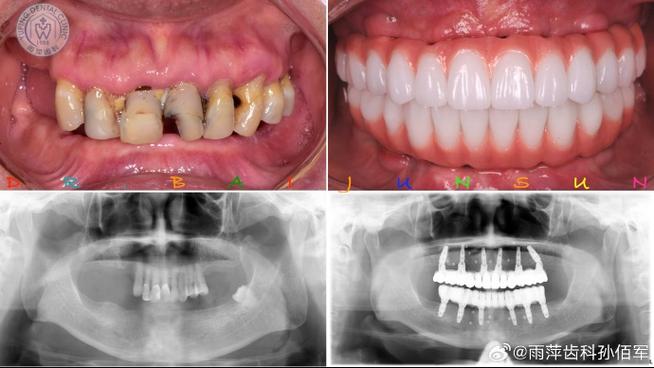

种植体周围组织愈合阶段的影响不可忽视,种植体植入后,需要与牙槽骨通过“骨结合”形成稳定连接,这一过程通常需要3-6个月,在此期间,种植体周围的牙龈、牙槽骨仍处于修复状态,咬合刺激可能引发组织水肿或轻微炎症,导致咬合感知异常,尤其是术后1个月内,咀嚼功能未完全恢复,咬合碰感可能更明显。

针对不同原因,医生会采取针对性处理:若为咬合高点,可通过精细调磨牙冠表面,去除早接触点,使咬合力分布均匀;若为种植体周围组织愈合期不适,可能需暂时调整咬合,避免患侧咀嚼,配合药物促进炎症消退;若修复体存在质量问题(如冠形态异常、边缘不密合),则需重新制作牙冠;若出现种植体松动或感染,则需评估是否需要进一步治疗,甚至重新种植。

需特别注意的是,切勿自行调磨牙冠,非专业人员无法准确判断咬合高点位置,盲目打磨可能导致咬合过低,影响咀嚼效率,甚至损伤牙冠或对颌牙,新植牙后需严格遵循医嘱定期复查(通常术后1周、1个月、3个月、6个月),医生会通过复查动态观察咬合关系、种植体骨结合情况及口腔健康状况,及时调整处理潜在问题,确保种植牙长期稳定使用。